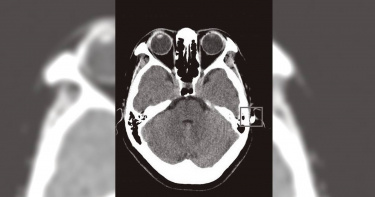

嘉義市興業東路10日上午發生一起休旅車與機車撞擊事故,70歲林姓機車女慘被壓在車底下,有熱心民眾見狀,開來堆高機架高休旅車,當時林姓婦人雖驚魂未定,仍自行爬出脫困,沒想到當時僅外表有多處擦傷的婦人,隔天中午卻宣告不治,因事發現場旁有1輛違規停放的自小客車,警方正釐清是否和車禍發生有關。熱血司機見狀,主動加入救援行列,出動堆高機將休旅車架高。(圖/取自湖內分隊臉書/中國時報呂妍庭嘉義傳真)林姓婦人當時受困休旅車下,車子架高後,婦人自行爬出。(圖/取自湖內分隊臉書/中國時報呂妍庭嘉義傳真)嘉義市消防局表示,當天湖內分隊救護車執行救護勤務返隊途中,行經興業東路看見一輛休旅車與機車碰撞,女騎士被壓在車底動彈不得,當下消防人員立刻下車處理,並通報救助器材車前來支援。正值危急時刻,一輛載著堆高機的拖板車恰巧經過,熱血司機見狀,主動加入救援行列,出動堆高機將休旅車架高,受傷林姓婦人在大家搶救下,順利爬出脫困,當時意識清楚,還能站起來,由消防員攙扶坐到擔架上,送往嘉義基督教醫院治療。嘉義市警察局交通隊今(13日)表示,43歲許姓女子駕駛自小客車10日上午10點39分左右,由吳鳳南路左轉興業東路時,與騎機車沿興業東路往東方向的70歲林姓婦人發生碰撞,林女一度受困休旅車下,身體多處擦傷、意識清楚,脫困後送醫治療,雙方當事人經酒測均無飲酒情事,不料,11日中午12點11分傳出林女宣告不治。檢警昨(12日)相驗,初步研判林婦因腹腔嚴重出血致命,因事發現場旁有1輛違規停車的自小客車,警方將調查林婦是否為閃避違停車輛而發生車禍,進一步釐清發生車禍的因果關係,目前已將違停的車主林姓男子列為關係人,並通知到案說明。